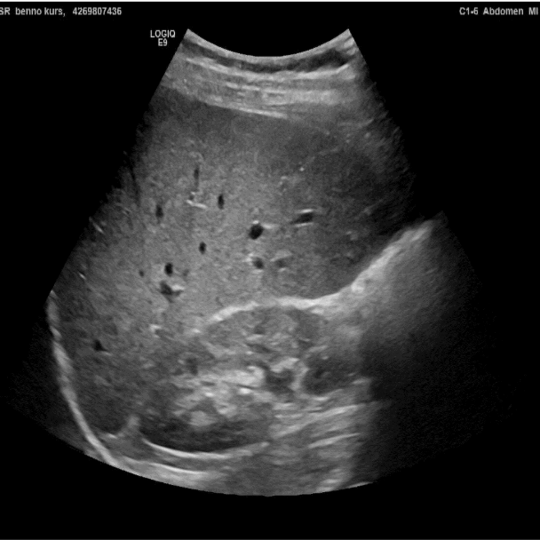

Ultraschall hat im Vergleich zu anderen bildgebenden Verfahren relativ geringe technische Anforderungen. Daher kann er für die klinische Beurteilung dort eingesetzt werden, wo der Patient oder die Patientin behandelt wird. Damit entfallen hohe Kosten und logistische Hürden, wodurch auch der finanziell benachteiligten Landbevölkerung kann eine professionelle Diagnostik angeboten werden. Point-Of-Care-Ultraschall (POCUS) wird durch das behandelnde medizinische Personal zur Beantwortung einer spezifischen klinischen Frage eingesetzt, um die Patientenversorgung und -betreuung zu unterstützen. POCUS ist relativ leicht zu erlernen und kann nach standardisierten Protokollen durchgeführt werden, wobei die Befunde leicht zu erkennen sind. Neben der Bestätigung einer akut behandelbaren Diagnose ist damit auch eine niedrigschwellige und kostengünstige Ersteinschätzung des Patienten oder der Patientin möglich.

POCUS kann bei Infektionskrankheiten wie Lungenentzündung, Tuberkulose oder Schistosomiasis, aber auch bei nicht übertragbaren Krankheiten wie Krebs und Leberzirrhose oder bei Notfällen wie Herzversagen oder Trauma eingesetzt werden. Der Einsatz von POCUS kann die Differentialdiagnose schnell eingrenzen, die Zeit bis zur endgültigen Behandlung verkürzen, die Ausfall- und Komplikationsraten bei Behandlungen verringern und die Patientenzufriedenheit verbessern. POCUS ist daher eine wichtige Innovation und dient der Optimierung der medizinischen Versorgung für die finanziell benachteiligte Bevölkerung.